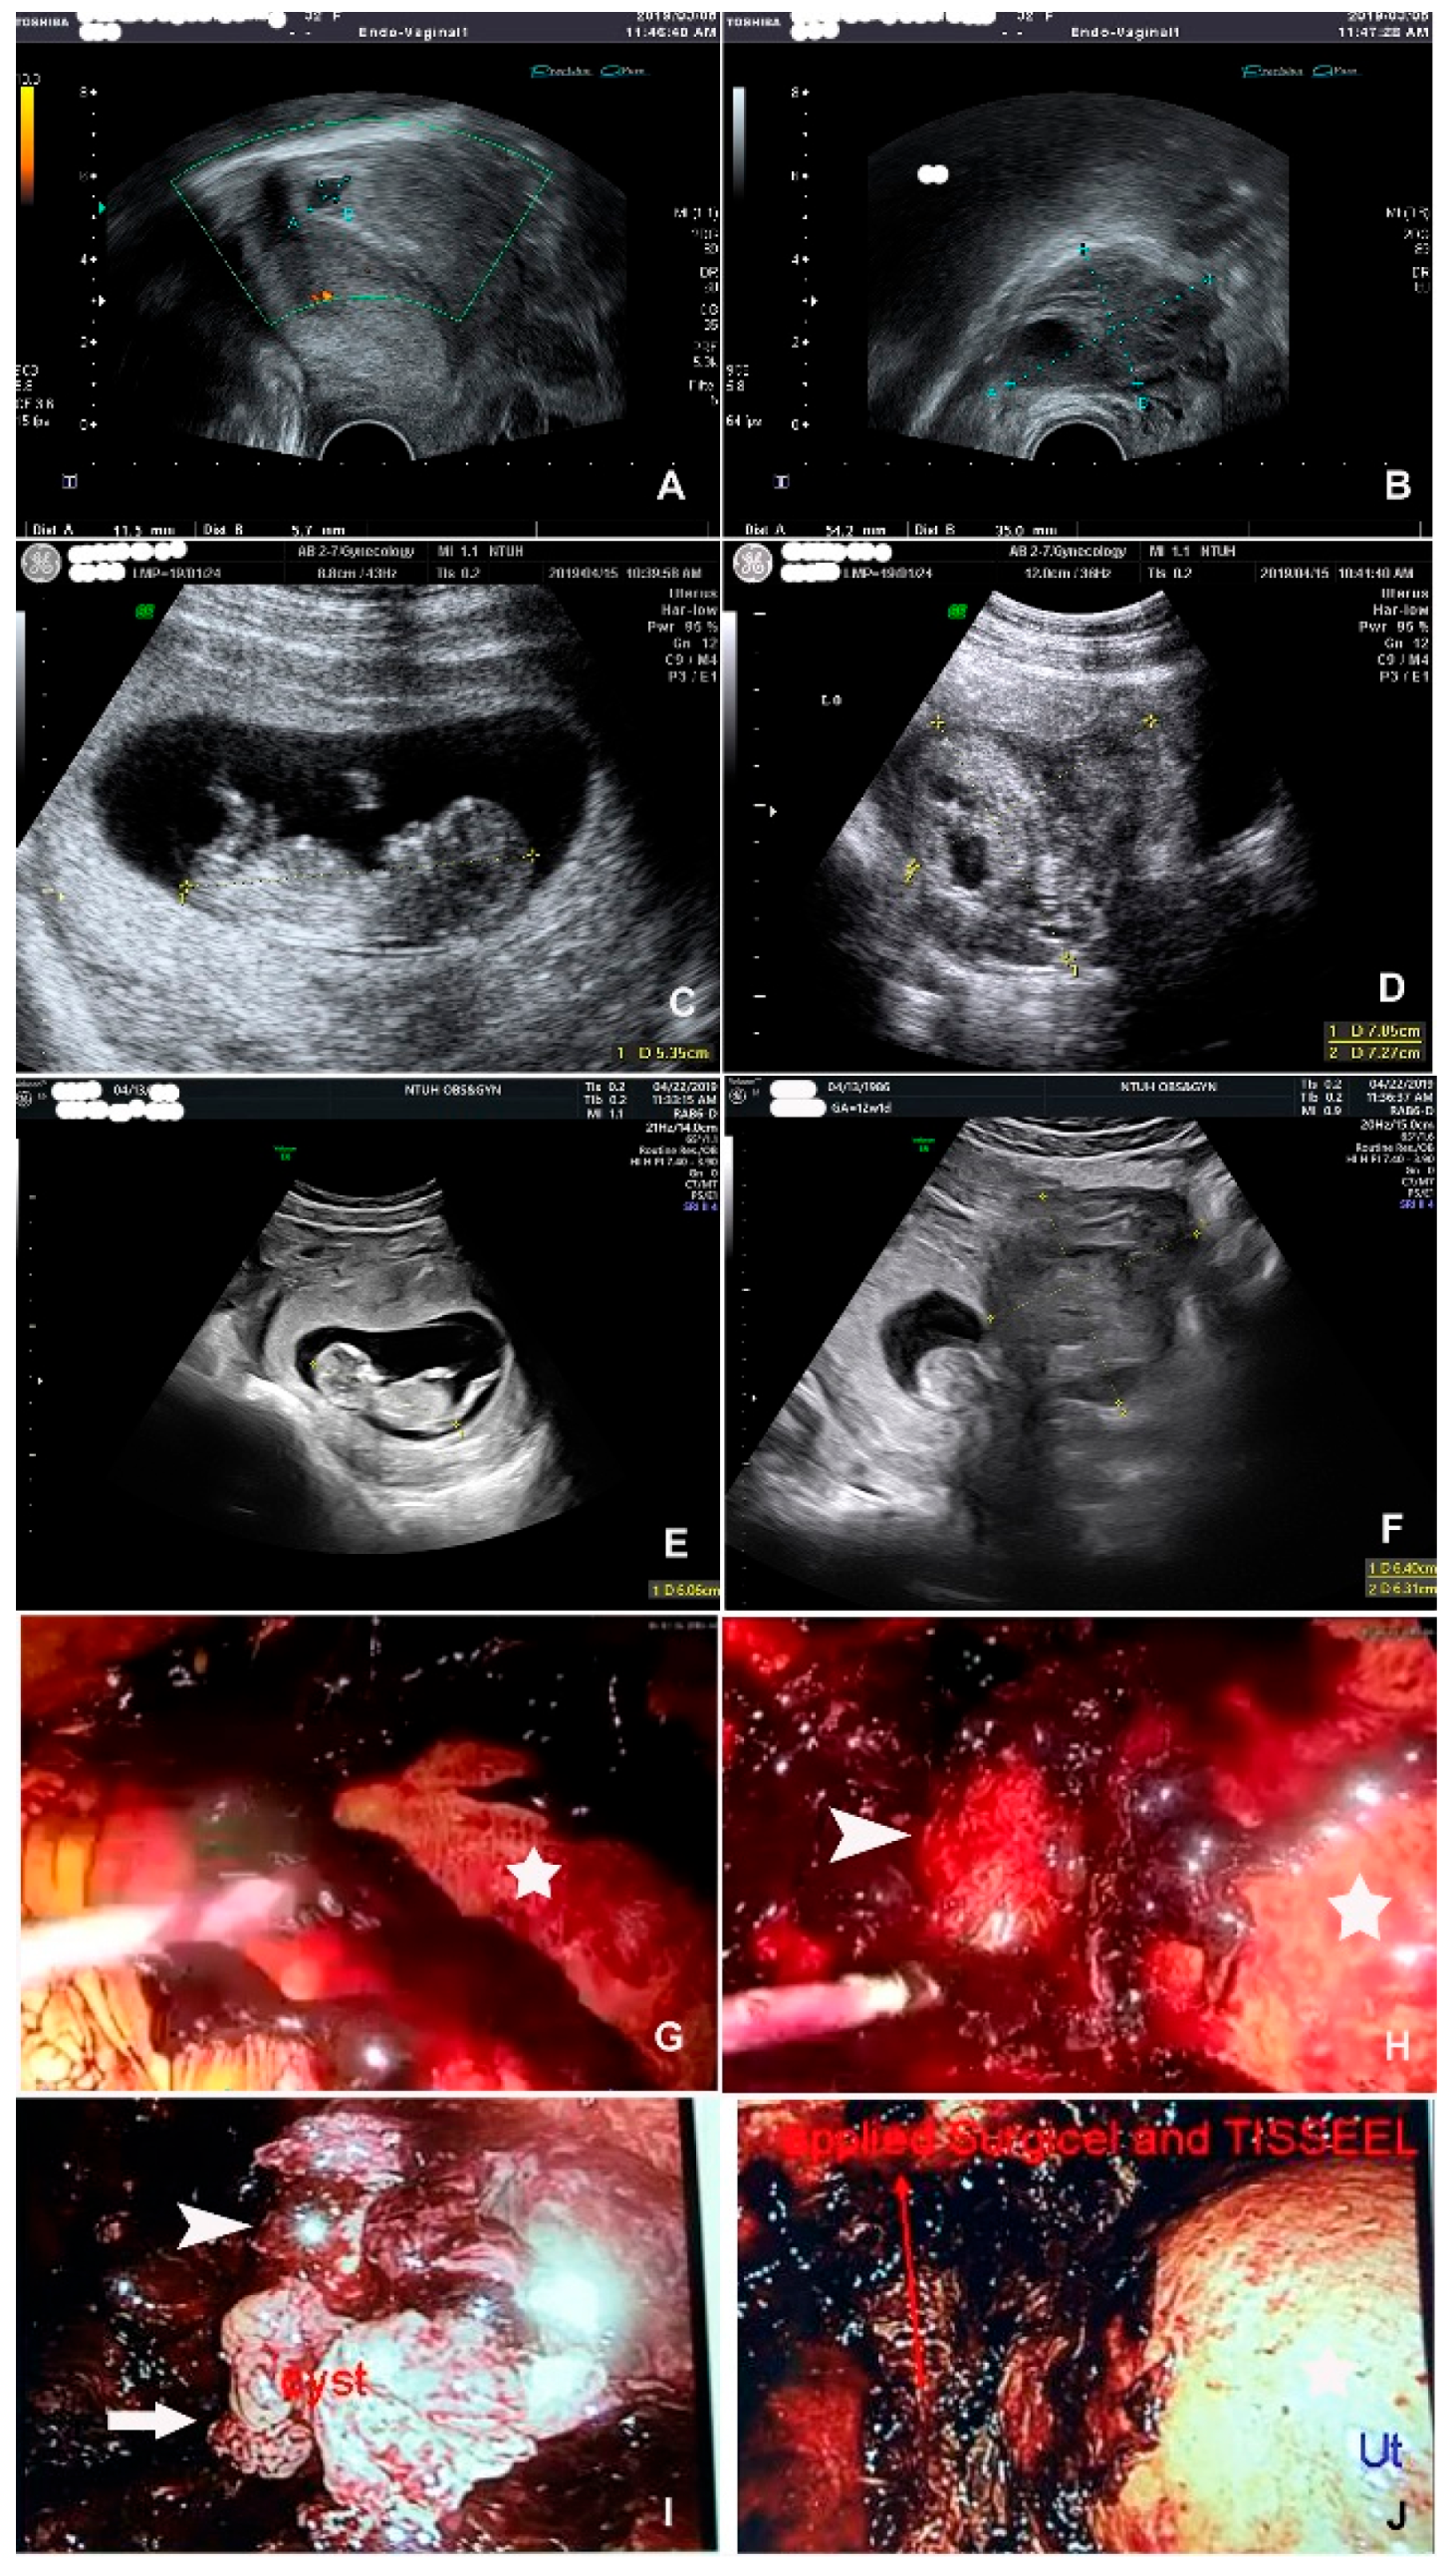

3.1.1. Case 1: Seromucinous Borderline Tumor (GA of 8 Weeks)

3.1.2. Case 2: Teratoma (GA of 10 Weeks)

3.1.3. Case 3: Heterotopic Pregnancy (GA 12 of Weeks)

3.1.4. Case 4: Mucinous Tumor (GA of 21 Weeks)